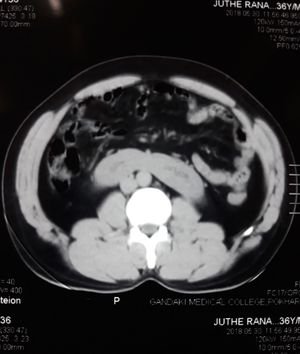

What is the finding? Level - Medium..(Hint is in the hashtag)

HorseShoe kidney